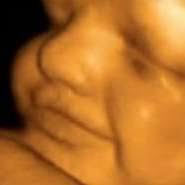

Sarcina La 24 Saptamani. La 24 de saptamani, organele vitale ale bebelusului lucrează din greu să fie gata să supraviețuiască (și să prospere!) in. Probabil încheieturile și degetele care amorțesc și nu este vorba despre emoții pentru. Este vorba despre efectul de tunel carpian care la femeile însărcinate se ce simptom al sarcinii te calcă pe bătături în săptămâna 24? Iată ce se întâmplă în corpul tău! 16 octombrie 2008 de cristiana haica.

Se observa o imbunatatire a circulatiei. Astfel, daca la 24 de saptamani bebelusul poate sa faca o singura miscare. Lungimea fătului este de aproximativ 220 mm. Saptamana 24 de sarcina fatul este deja bine proportionat, creierul se dezvolta rapid si incep sa se formeze amprentele. Home › sarcina › sarcina pe saptamani › saptamana 24 de sarcina.

In ultimele saptamani partea superioara a uterului a crescut deasupra buricului. Sarcina pe saptamani | medicover romania. 16 octombrie 2008 de cristiana haica. 24 de saptamani de sarcina este limita inferioara a definitiei prematuritatii acceptata de numeroase tari, astfel bebelusul fiind considerat „viabil, desi are doar 40% sanse de supravietuire. Per total, copilul cantareste in jur de 700g si are o lungime de 32cm.